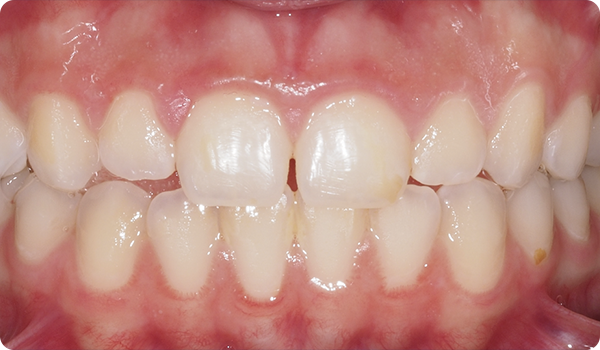

Sourires en place

Grâce à Right, vos patients obtiendront le sourire qu'ils souhaitent quand ils le souhaitent, de manière confortable et indétectable.

L'alignement des dents avec Right est la solution parfaite et la plus conservatrice pour les futurs traitements de blanchiment ou de facettes. Elle apportera la perfection au sourire du patient.